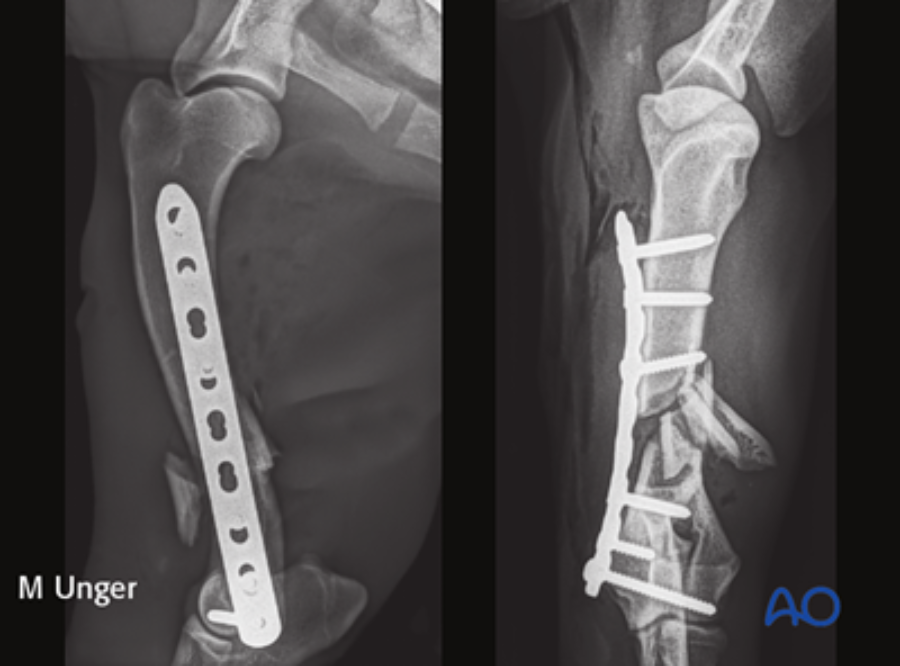

The module on this anatomical area was authored by Martin Unger (Germany). Matthew J Allen (UK) and Aldo Vezzoni (Italy) acted as editors.

It encompasses both nonsurgical and surgical management techniques, providing detailed insights into the utilization of plates, intramedullary pins, and interlocking nails for fixation. Additionally, it offers supplementary reading materials that highlight the anatomical distinctions between dogs and cats, as well as the most prevalent complications that arise during humeral shaft fracture management.

Once an initial version was completed, the module underwent a rigorous evaluation process. Esteemed professionals in the field, including Amy Kapatkin (executive editor), Aldo Vezzoni (general editor for thoracic limb), and Matthew Allen (AO VET’s incoming executive editor), meticulously reviewed it. Their invaluable insights and recommendations, including the addition of further case examples, were thoughtfully incorporated. This phase of review and quality control ensured a robust and comprehensive module even before the final version was produced.